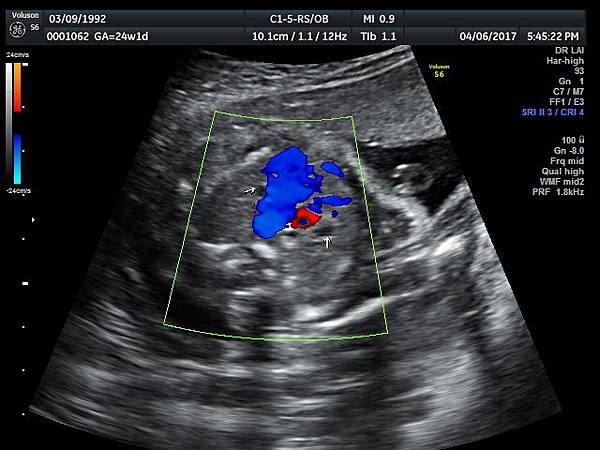

2017年4月6日25歲第一胎自然懷孕24週1天的孕婦,在我的診所接受胎兒心臟及高層次超音波檢查,檢查結果是持續性左側上腔靜脈(PLSVC)(附圖 4~6)合併輕微三尖瓣逆流,她的四指標篩檢唐氏症和愛德華氏症都是低風險,我的建議是抽羊水做傳統染色體及基因晶片檢查,如果擔心羊穿風險,可退而求其次做NIPS檢查。

47 24 weeks isolated PLSVC